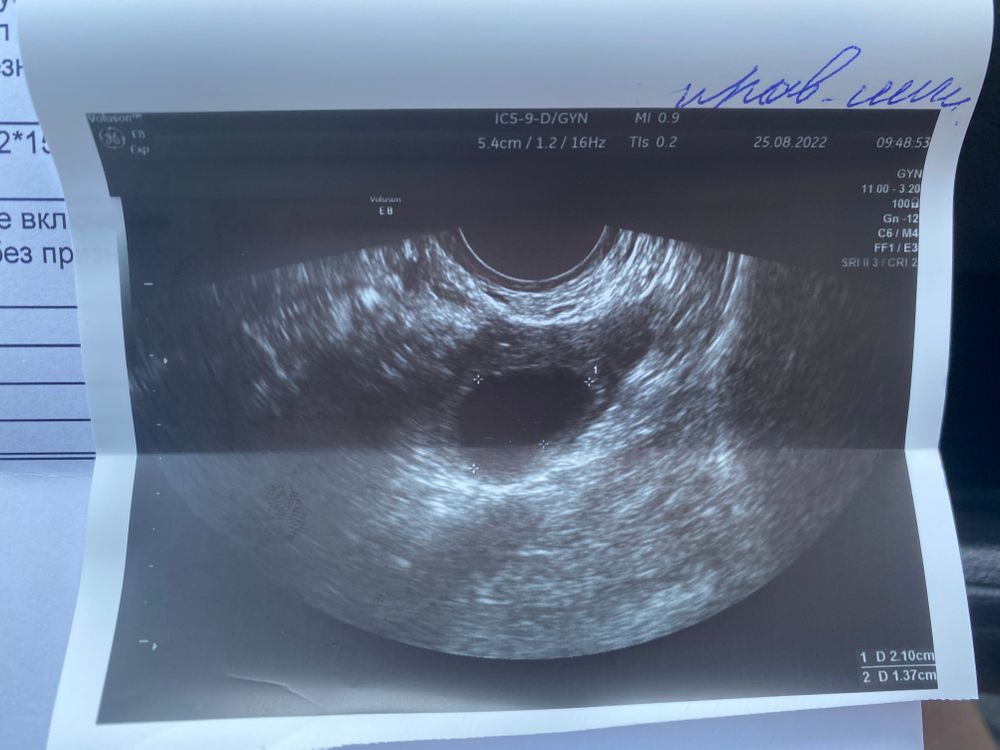

Всем привет, сегодня 18 ДЦ, ранее писала про стимуляцию и овитрель, сегодня была на фолликулометрии мой фолликул так и держится в размерах, 21*14мм, но сегодня она сказала что эндометрий так выглядит как будто овуляция всё-таки произошла, может говорит яйцеклетка вышла и это вовсе не фолликул там сидит, а просто желтое тело осталось, было у кого-то так же?) фото прилагаю

Добрый день, по фото так сложно определять жт или дф это, определяют по кровотоку, про котрый пишут что его нет, может еще только формируется

Ольга, А эндометрий это с последнего узи фото, просто он на ней не очень похож на секреторный, у него четко слои просматриваются, я в интернете смотрела фото мэхо второй фазы так он там весь одного цвета без линий, более светлый становится, но я ж не врач, похоже что еще одно узи нужно, что б наверняка, а по БТ вы не следите была или нет овуляция